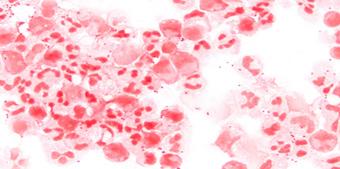

Pueden incluir marcadores inflamatorios elevados (velocidad de sedimentación globular y/o proteína C reactiva elevada), anemia normocrómica - normocítica y factor reumatoide positivo.

CRITERIOS MAYORES

Hemocultivos positivos (95% de casos) para microorganismos típicos:

Estreptococos, Estafilococo y Enterococo

En caso de Coxiella Burnetii serología: IgG anticuerpo > 1:8000 Ecocardiografía positiva (80 % de casos)

2 (ENAM 2011) (ENARM 2015) (ENAM EXTRA 2020) (ENAM EXTRA 2023) 1

Masa oscilante sugerente de verruga o absceso o dehiscencia de prótesis.

Nueva regurgitación valvular (el aumento o cambio en el soplo preexistente)